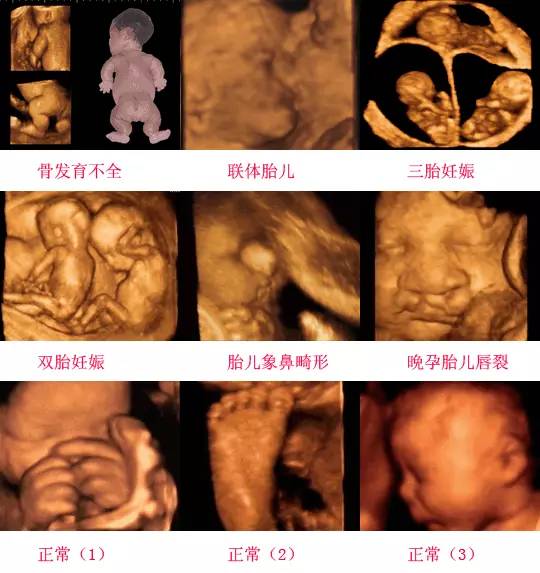

四維彩超是一種先進(jìn)的醫(yī)學(xué)影像技術(shù),通過實時觀察胎兒在母體內(nèi)的活動情況,為醫(yī)生提供了豐富的診斷信息,在四維彩超下,我們可以清晰地觀察到胎兒的蛋蛋(睪丸)的形態(tài)、位置和大小等特征,胎兒蛋蛋是男性生殖系統(tǒng)的重要組成部分,對于胎兒的生長發(fā)育具有重要意義。

在四維彩超下,胎兒蛋蛋呈現(xiàn)出特定的形態(tài)和外觀,通常情況下,胎兒蛋蛋呈現(xiàn)出圓形或橢圓形,表面光滑,內(nèi)部回聲均勻,隨著胎兒的發(fā)育,蛋蛋會逐漸增大,并呈現(xiàn)出明顯的性別特征,醫(yī)生可以通過四維彩超技術(shù),對胎兒蛋蛋的大小、形態(tài)和位置進(jìn)行評估,以判斷胎兒生殖系統(tǒng)的健康狀況。

四維彩超技術(shù)在評估胎兒蛋蛋發(fā)育方面具有重要意義,通過四維彩超,醫(yī)生可以實時觀察胎兒蛋蛋的形態(tài)、位置和大小等特征,了解胎兒生殖系統(tǒng)的發(fā)育情況,四維彩超還可以幫助醫(yī)生發(fā)現(xiàn)可能的異常情況,如睪丸未降、睪丸囊腫等,為及時采取治療措施提供依據(jù)。